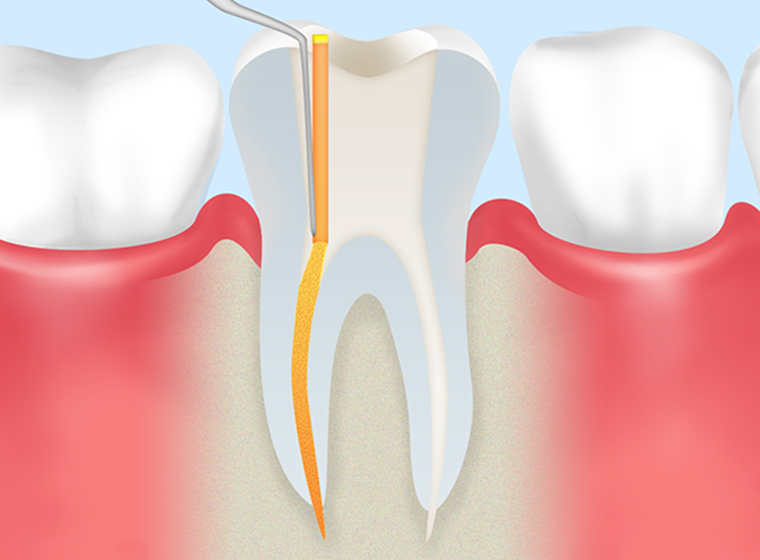

歯の神経や血管が入っている細い管を「根管」といいます。その中からむし歯に汚染された神経や血管、歯質を除去して細菌を残さないように洗浄・消毒してから、薬剤をすき間なく注入して密閉する処置を「根管治療」といいます。治療した箇所には土台を作り、被せ物を装着して歯の機能を補います。

- STEP1

むし歯の除去 -

- STEP2

根管内の洗浄と計測 -

- STEP3

根管内の消毒・除菌 -

- STEP4

薬剤の充填 -